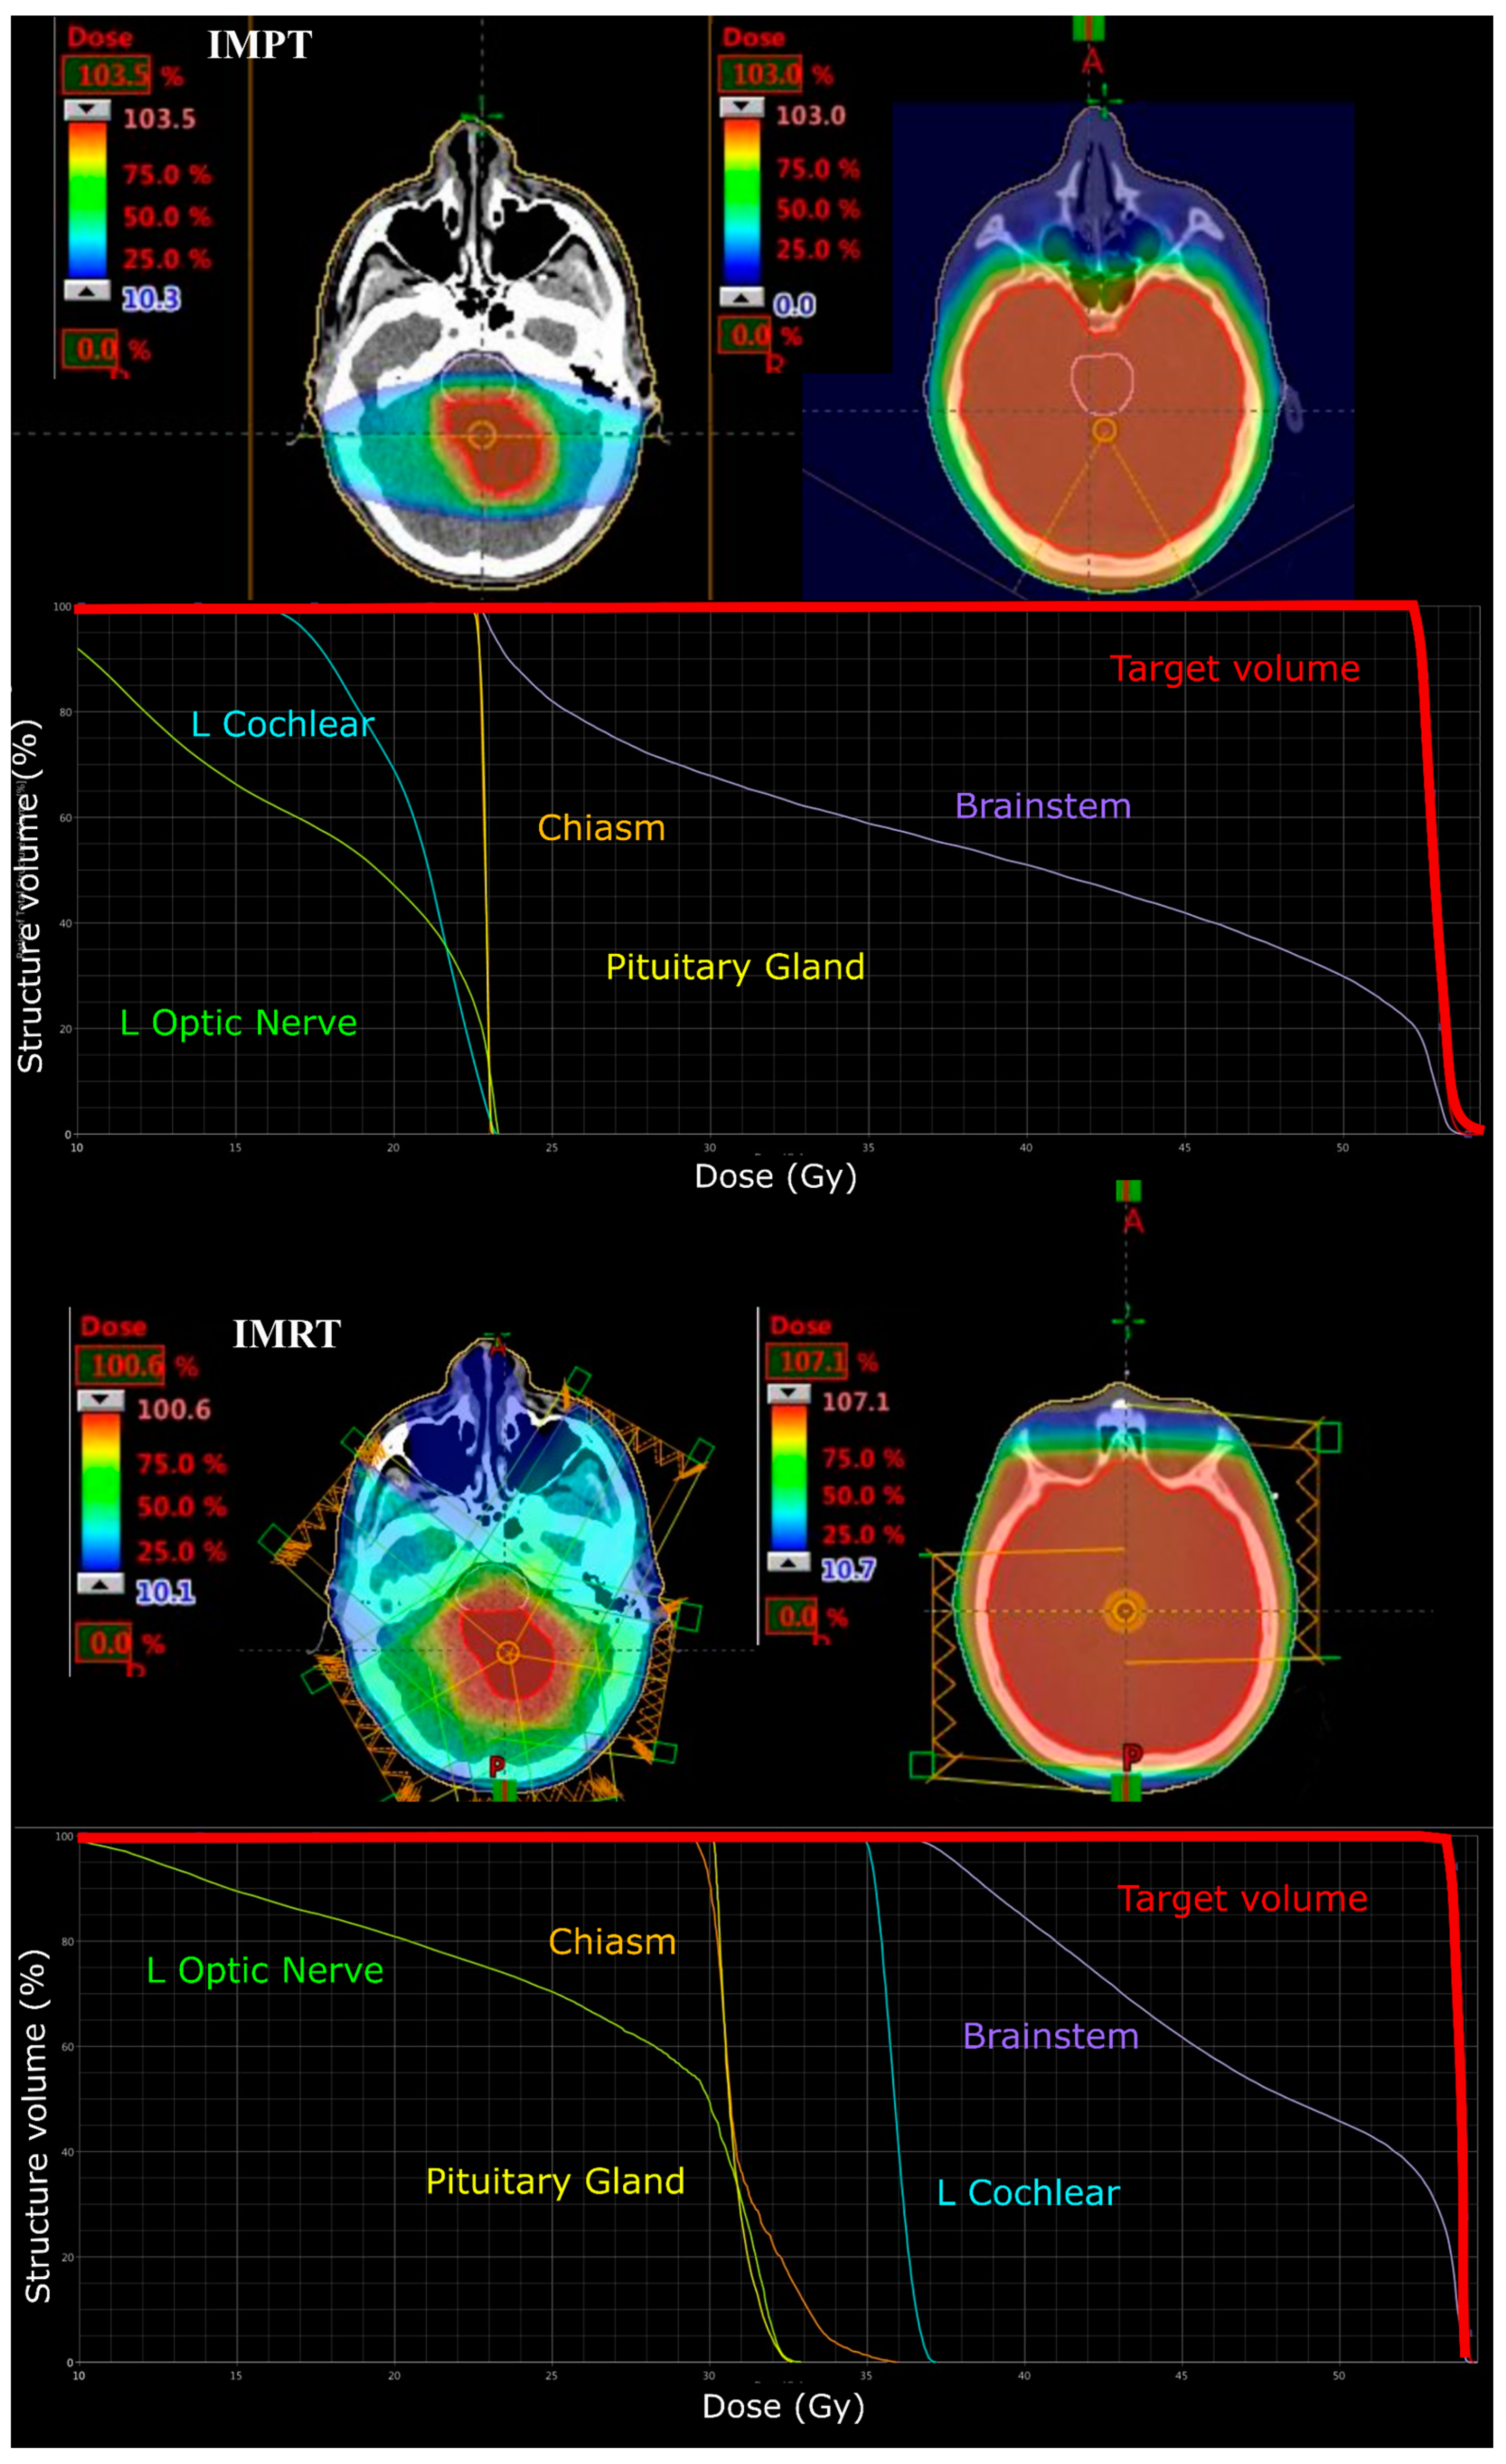

Two posterior-oblique beams were generated to deliver a CSI dose of 23.4 Gy (RBE) to the entire brain in IMPT treatment plans for MB. For 5 and 9-year-old CSI phase plans an additional posterior field was added to improve the coverage of all cranial contents due to the smaller separations of the brain. A primary site boost to 54 Gy (RBE) was then planned to the CTV using two lateral beams with a couch kick angle of 20° to the avoid mastoid air cells and thickest portion of the skull.

All IMRT plans were planned to deliver a prescription of 54 Gy (1.8 Gy per fraction). Five co-planar IMRT photon fields of 6 MV energy were required (gantry angles: 30, 100, 170, 240 and 310 degrees) to adequately cover the target volume (see Figure 2). IMRT plans were optimised to similarly deliver a CSI dose of 24 Gy via opposed lateral fields and a 30 Gy boost phase using a five field co-planar arrangement (see Figure 3).

Figure 3. Colourwash dose distributions and dose–volume histograms for a 13-year-old male with infratentorial medulloblastoma. Typical planning beam arrangement viewed on axial CT images for IMPT tumour bed (top left) and craniospinal (top right) and IMRT tumour bed (bottom left) and craniospinal (bottom right) plans. Respective dose–volume histograms are shown below.